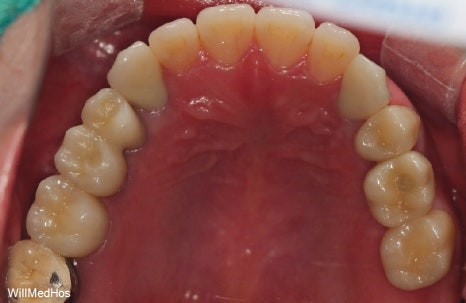

위의 사진이 최종 치료 사진 입니다. 뼈이식, 신경치료 후 크라운, 임플란트 치료를 진행 하였고

최종 기간은 10개월 정도 소요 되었습니다.

▲ 최종 완료 구강 사진